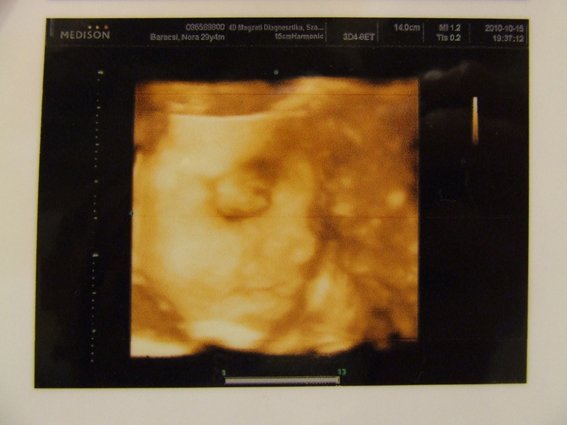

Bocsi, most kicsit rövid és önző leszek, most megyünk 4D-re!!! :)

Majd jövök fotókkal és olvasgatok is majd, mert úgy látom elég sok minden volt megint.